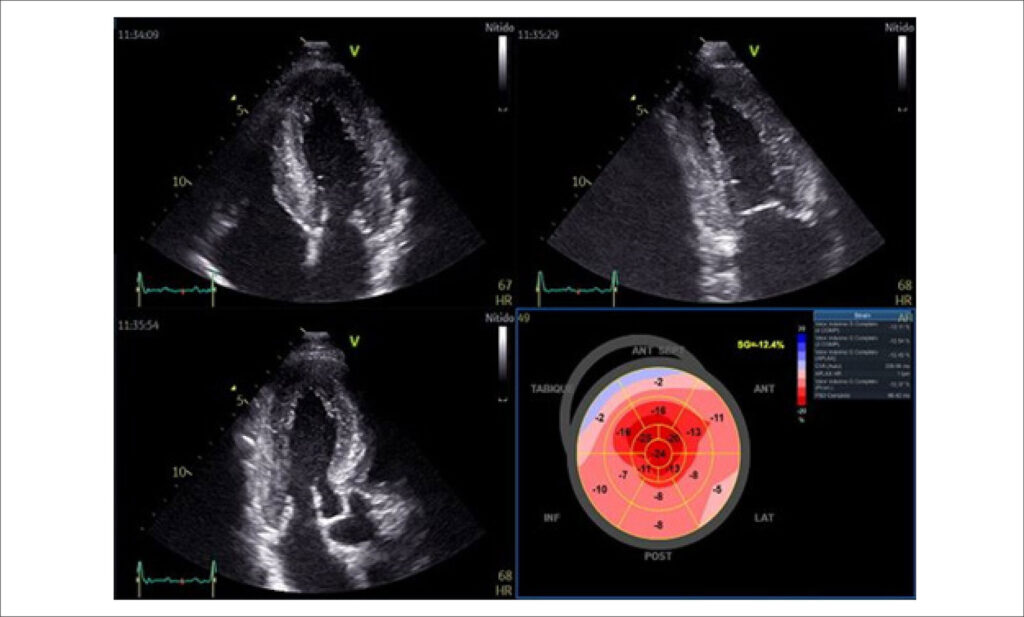

A amiloidose cardíaca por transtirretina (TTR) era considerada uma doença rara, com prognóstico ruim devido à falta de tratamento efetivo e à detecção desafiadora. Isso mudou nos últimos anos, com um aumento na prevalência e incidência da doença devido a um melhor reconhecimento da doença, à disponibilidade de novos métodos diagnósticos e aos tratamentos modificadores da doença. Apresentamos o caso de um paciente do sexo masculino de 62 anos, com sinais e sintomas de insuficiência cardíaca associada a envolvimento do sistema nervoso periférico e disfunção autonômica. O uso de ecocardiograma transtorácico, ressonância magnética cardíaca, cintilografia cardíaca, análise de cadeias leves no sangue e teste genético possibilitou o diagnóstico de amiloidose por TTR (ATTR) do tipo selvagem (ATTRs).